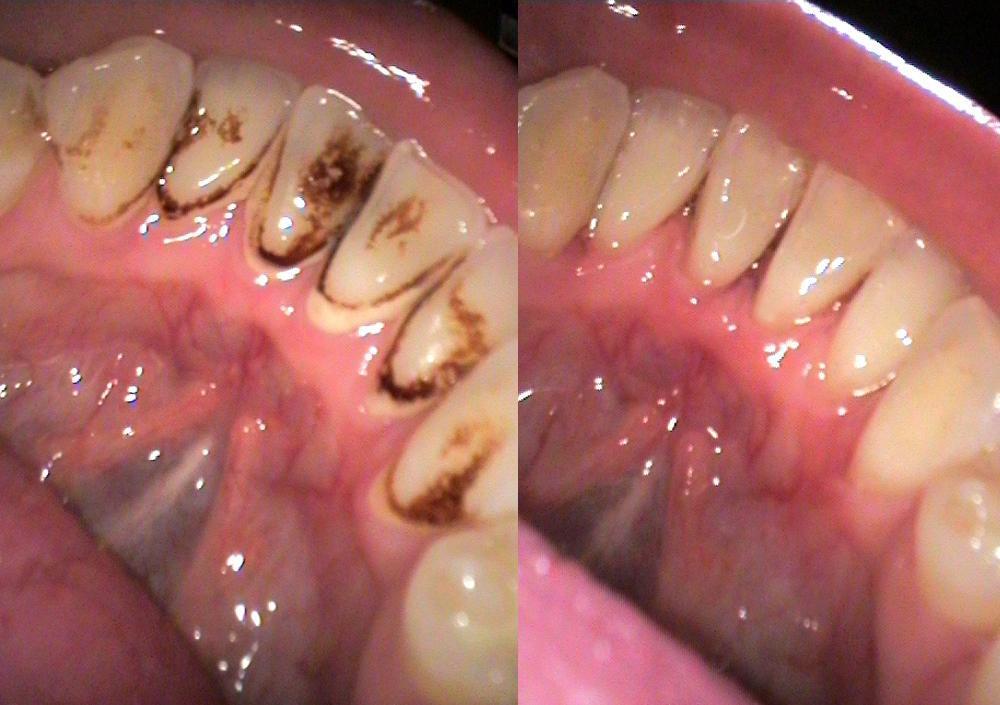

Догляд за зубами з металокераміки повинен бути такий самий, як і для решти зубів. Незважаючи на їх стійкість, наліт від фарбуючих напоїв, сигарет може змінювати їх колір. Тому догляд їм також потрібний регулярний. Це обов'язкове чищення зубною щіткою та пастою, використовуючи для цього придатні пасти та правильні кругові рухи (які повинні вимітати залишки їжі та наліт). Після їди, необхідно ретельно прополоснути рот. Для щелепи, яка вся складається з протезів, більше основного догляду не потрібно. Але необхідні додаткові заходи для очищення сторонніх тіл з-під протезованих зубів, а також догляд за яснами, який забезпечить іригатор. Саме він очистить порожнину рота в тому випадку, якщо стороннє тіло (наприклад, залишок їжі) застрягне між звичайним зубом і металокерамічною коронкою.